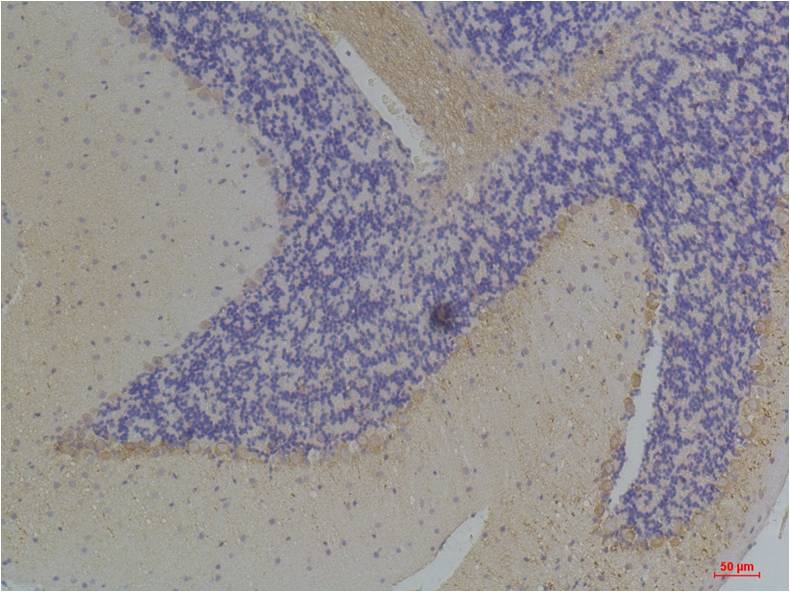

Immunohistochemical analysis of paraffin-embedded Rat BrainTissue using?KChIP3 (EA305)Rabbit pAb diluted at 1:200.

Immunohistochemical analysis of paraffin-embedded Mouse BrainTissue using?KChIP3 (EA305)Rabbit pAb diluted at 1:200.